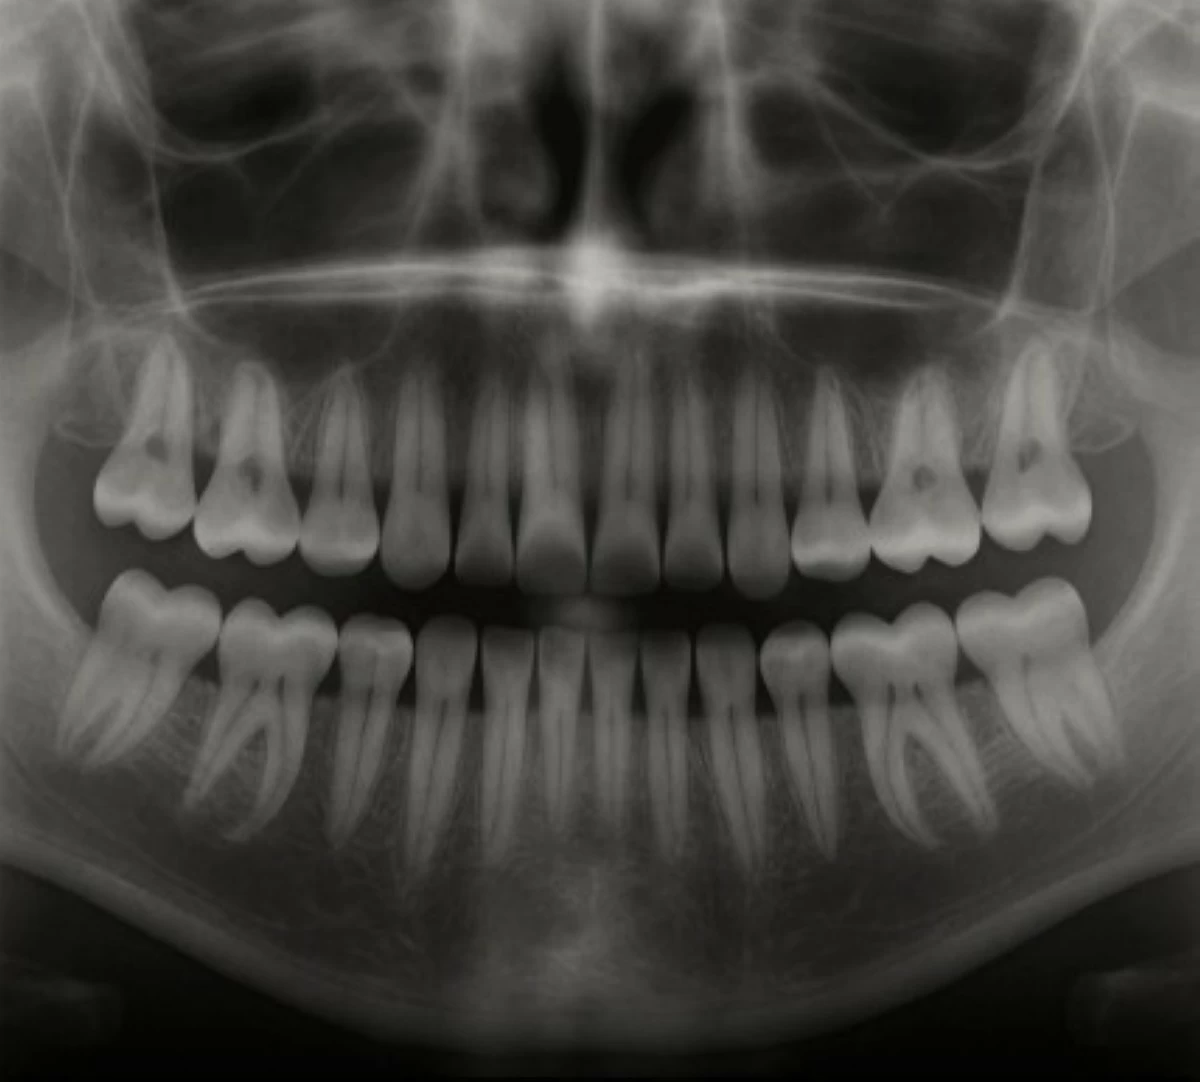

ابتكر علماء في اليابان دواءً يُمكّن البشر من استعادة نمو أسنانهم المفقودة بشكل طبيعي!

يعمل هذا الدواء، الذي ابتكره باحثون بقيادة الدكتور كاتسو تاكاهاشي في معهد الأبحاث الطبية بمستشفى كيتانو، عن طريق تثبيط بروتين يُسمى USAG-1، والذي يُثبّط نمو الأسنان عادةً.

في التجارب التي أُجريت على الفئران، نجح هذا التثبيط في تحفيز نمو أسنان جديدة تمامًا، ويستعد الفريق الآن لتجارب سريرية على البشر بهدف إتاحة العلاج للجمهور بحلول عام 2030.

في حال نجاحه، يُمكن لهذا العلاج أن يُحدث نقلة نوعية في رعاية الأسنان من خلال منح الناس فرصة ثالثة لنمو أسنانهم.